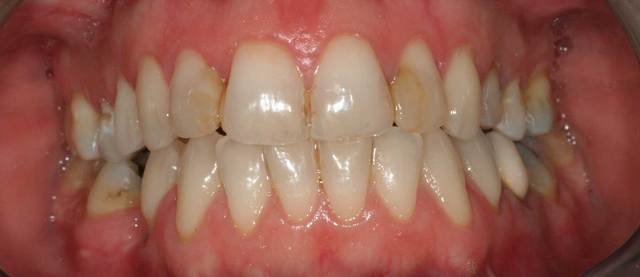

Si j'ai bien compris:

- il y a un verrou à gauche mais pas à droite, donc situation à risque.

- La contention est en haut alors qu'elle devrait être en bas.

43 sur 12 et 13 sur 44 qui commence deja a faire la gueule ( fente de stillman? on voit pas bien )

l'autre coté, j'aimerai voir en mouvement